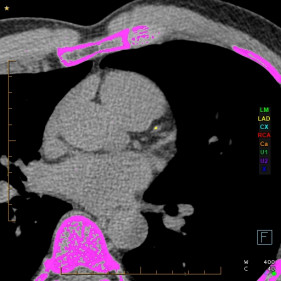

Heart Health Check - A simple scan that could save your life

When it comes to your heart, early detection of potential issues is key. One of the most effective ways to assess your heart health is through a CT Calcium Score, a quick and non-invasive scan that can provide crucial insights into your risk of heart disease.

A CT Calcium Score is a quick, non-invasive scan that measures the amount of calcium buildup in your heart’s arteries. This calcium is a sign of atherosclerosis, or hardening of the arteries, which increases your risk of a heart attack.

A CT Calcium Score scan is simple, fast, and does not require any injections or contrast. You will lie on a scanning table, and a low-dose CT scanner will take images of your heart in just a few minutes. The results are then analysed by one of our specialists, and a calcium score is provided. We may also provide you with an adjusted risk of a coronary event.

Your calcium score helps determine your level of risk:

• 0             Very low risk (no coronary calcium)

• 1 - 100       Low risk (mild plaque build-up)

• 101 - 400  Moderate risk (significant plaque build-up)

• >400       High risk (requires further assessment and management)

The higher your score, the higher your risk of a heart attack or other heart-related event.